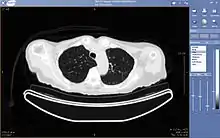

Teleradiology is the ability to send radiographic images (x-rays, CT, MR, PET/CT, SPECT/CT, MG, US...) from one location to another.[74] For this process to be implemented, three essential components are required, an image sending station, a transmission network, and a receiving-image review station. The most typical implementation are two computers connected via the Internet. The computer at the receiving end will need to have a high-quality display screen that has been tested and cleared for clinical purposes. Sometimes the receiving computer will have a printer so that images can be printed for convenience.

The teleradiology process begins at the image sending station. The radiographic image and a modem or other connection are required for this first step. The image is scanned and then sent via the network connection to the receiving computer.

Today's high-speed broadband based Internet enables the use of new technologies for teleradiology: the image reviewer can now have access to distant servers in order to view an exam. Therefore, they do not need particular workstations to view the images; a standard personal computer (PC) and digital subscriber line (DSL) connection is enough to reach Keosys' central server. No particular software is necessary on the PC and the images can be reached from anywhere in the world.

Teleradiology is the most popular use for telemedicine and accounts for at least 50% of all telemedicine usage.